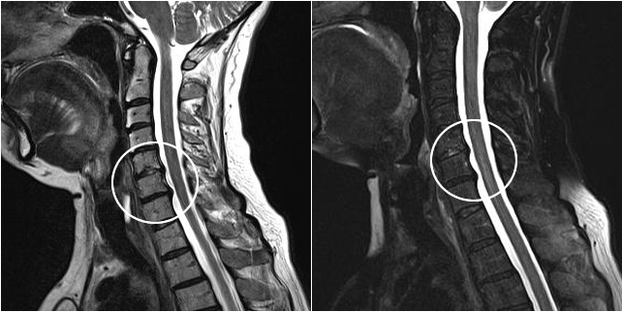

Modern diagnostic methods include MRI and CT, which help most accurately examine the processes that destroy cartilage and bone tissue.In addition, using this technique will facilitate the diagnosis of hernias and other soft tissue defects near the source of the disease.